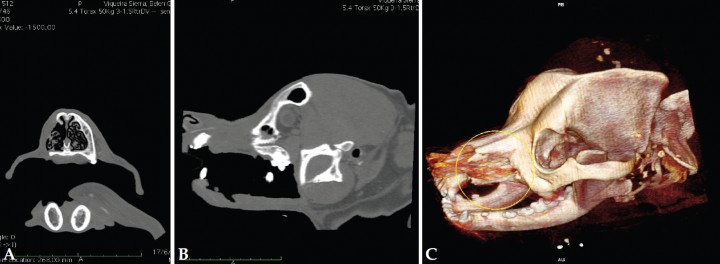

Transcurridos 6 meses de la intervención quirúrgica se realizó un estudio TAC craneal (Fig. 8) y torácico de seguimiento. En el área del maxilar izquierdo se apreció una buena evolución, sin presencia de bordes óseos irregulares ni crecimiento de tejidos blandos periféricos en la zona de intervención. La cavidad nasal no presentaba proceso de inflamación, secreciones anómalas o captación anómala de contraste en la secuencia post contraste. Los nódulos linfáticos regionales tenían un aspecto normal. En el tórax no se observaron alteraciones.

<p>Imágenes de TAC con ventana de huesos 6 meses después de la cirugía. (A) Plano transversal (B) Plano sagital (C) 3D. Se observa ausencia de neoformación ósea y/o tejidos blandos en la región intervenida (imágenes cedida por Diagnosfera).</p>

Imágenes de TAC con ventana de huesos 6 meses después de la cirugía. (A) Plano transversal (B) Plano sagital (C) 3D. Se observa ausencia de neoformación ósea y/o tejidos blandos en la región intervenida (imágenes cedida por Diagnosfera).

La realización del TAC posquirúrgico ayudó a demostrar la curación clínica de la paciente, pues se realizó 6 meses después de la intervención quirúrgica, cuando la aparición posterior de recidiva ya sería improbable. El resultado funcional y estético en este caso clínico fue muy satisfactorio.